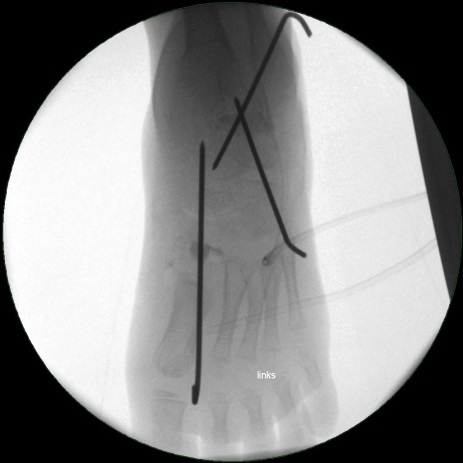

• Röntgenkontrolle (Bild 21,22).

• Im dargestellten Fall war zusätzlich eine plantarflektierende Cuneiforme mediale Osteotomie mit resorbierbarem Knochenersatz und eine Wadenmuskeldissektion nach Vulpius durchgeführt worden.

• Stabilisierung des Spanes mit Kirschnerdrähten (Bild 18).